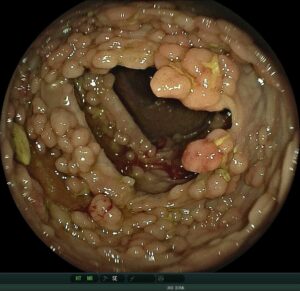

polyposis_bigger_AH